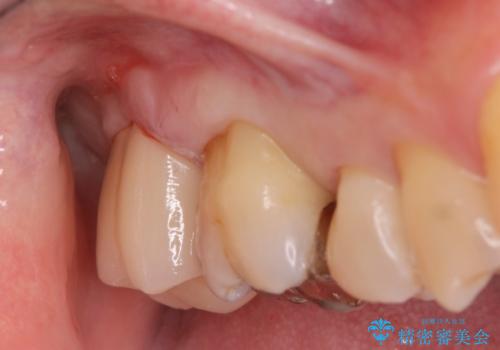

- ジルコニアクラウン・仮歯 12.1万円費用は治療当時の料金となります

適合の良い被せ物が入りました。

冷たいものがしみなくなり大変満足してもらいました。

一つ前の歯も後に染みてくる可能性があるとの事で被せ物をするか検討中です。